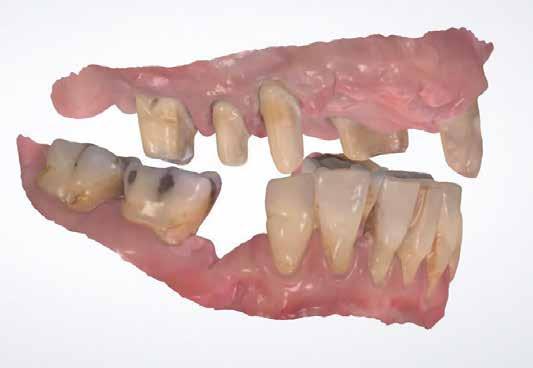

A kívánalmak szerint alul teleszkópos, cirkónium-dioxid stégre támaszkodó PEEK-vázas fogsor, felül teljes kivehető lemezes PMMA-fogsor készült.

A végleges munka készrevitele

A nyomtatott fogsorokat fizikai gyűjtőlenyomatként használtuk, az egyéni kanál helyett. Ez időt és erőforrást

martuk ki.

19–22. képek: A digitális fogsorokat fehér műanyagból, 3D nyomtatóval nyomtattuk.

23. kép: A szinterezett stégek.

takarított meg. Először kikerestük az analóg illeszkedő Vita Physiodens-sorozatú fogakat, és foganként, egyenként behelyettesítettük a nyomtatottak helyére (31-39. képek) . Szintereztük a kimart stégeket, majd magas fényre políroztuk őket (40.-41. képek) . A fogfelállításról szilikonblokkot vettünk (42.kép) . Az anatómiailag kicsinyített PEEK-váz tervezéséhez a fogakat bazálisan megcsiszoltuk, rögzítettük a blokkban, majd beszkenneltük. A beolvasott blokk a fogakkal segítette a vázredukció tervezését: annyi stabilitás, amennyi csak lehetséges egy plaszto-elasztikus vázanyaggal (43–46. képek) . Persze a poliéter-éterketon (PEEK) nagy teljesítményű műanyagra gondoltunk ezzel. A teljes biztonság érdekében a stégek végeire frikciós (csúszási súrlódást kihasználó – a ford.) segédelemek számára terveztünk befogadó fészkeket (47–48. képek) . A PEEK-váz sima felszínét – a kompozittal való biztos kötésére előkészítendő – behelyeztük

a vázakat a Diener Denta Plus plazmakészülék vákuumkamrájába, oxigén-nitrogén gázkeverékbe (49–50. képek) . Ez az eljárás csodálatosan retentív felszínt hoz létre a PEEK-vázon (51–53. képek) . Így előkészítve egyesítjük a blokkban rögzített gyári fogakat Vita VM CC műanyag segítségével a PEEK vázzal (54–58. képek) . A felső fogsor-alaplemezt rózsaszínű PMMA-ból készítettük, majd a két ötös között ezt redukáltuk az egyéniesítéshez (59. kép) . A munkát a Vita Akzent festékekkel és Vita VM LC gingivamasszákkal fejeztük be (60–66. képek) . A segédelemek befogadó helyeit műanyaggal töltöttük fel, amit igény esetén könnyen el lehet majd távolítani, így behelyezhetők lesznek a cirkonoxid-műanyag frikciós segédelemek (67–70. képek) . Végül a teljes szerkezetet a „Highfield-Clean-Prostethics” tisztítási elvének megfelelően (71. kép) plazmával fertőtlenítve csomagoltuk és küldtük a rendelőbe.

24–29. képek: A digitális mintákat az ellenőrzéshez fizikailag is kinyomtattuk, mert kiválóan megfeleltek az elkészült stégek szállítására a rendelőbe.

30. kép: Az okklúzió minimális korrekcióját követően a rendelőben újólag rögzítették a harapást, majd a 3D harapásregisztráló fogsorok visszakerültek a laborba. A stégek pozícióját funkciós lenyomatban rögzítették. A következő ülésben a viasz fogpróbát ellenőrizték szájban. Újra rögzítették a tovább finomított okklúziót.

31–39. képek: Következhetett a készrevitel. A kívánalmak szerint alul teleszkópos, cirkónium-dioxid stégre súrlódással illeszkedő PEEK-vázas fogsor, felül teljes kivehető lemezes PMMA-fogsor készült. Először kikerestük az analóg illeszkedő Vita Physiodens-sorozatú fogakat, és foganként, egyenként behelyettesítettük a nyomtatottak helyére.